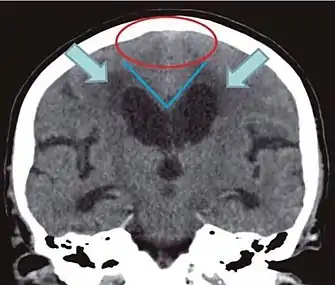

- Imaging from magnetic resonance imaging (MRI) or computed tomography (CT) is needed to demonstrate enlarged ventricles and no macroscopic obstruction to cerebrospinal fluid flow. Imaging should show an enlargement to at least one of the temporal horns of lateral ventricles, and impingement against the falx cerebri resulting in a callosal angle ≤ 90° on the coronal view, showing evidence of altered brain water content, or normal active flow (which is referred to as "flow void") at the cerebral aqueduct and fourth ventricle.

| CSF spaces over the convexity near the vertex (red ellipse | Narrowed convexity ("tight convexity") as well as medial cisterns | Widened vertex (red arrow) and medial cisterns (green arrow) |

| Callosal angle (blue V) | Acute angle | Obtuse angle |

| Most likely cause of leucoaraiosis (periventricular signal alterations, blue arrows |

Transependymal cerebrospinal fluid diapedesis | Vascular encephalopathy, in this case suggested by unilateral occurrence |